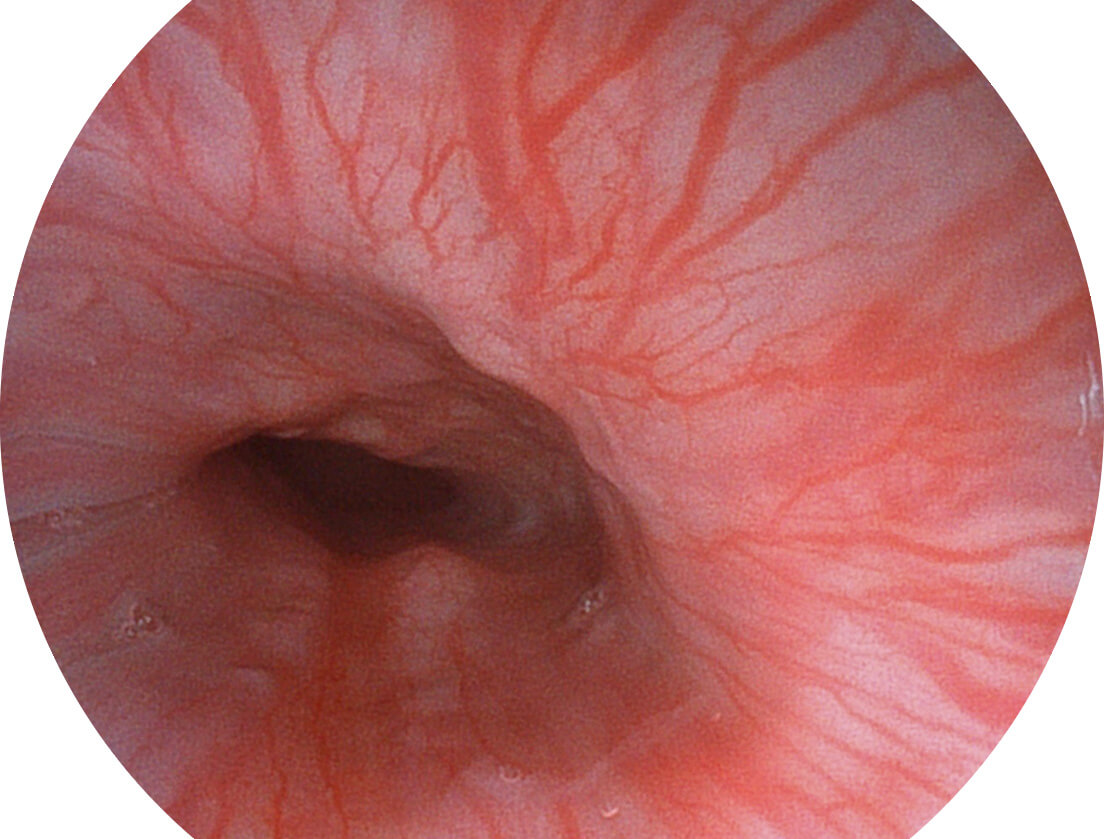

白光图像

SFI图像

VIST图像